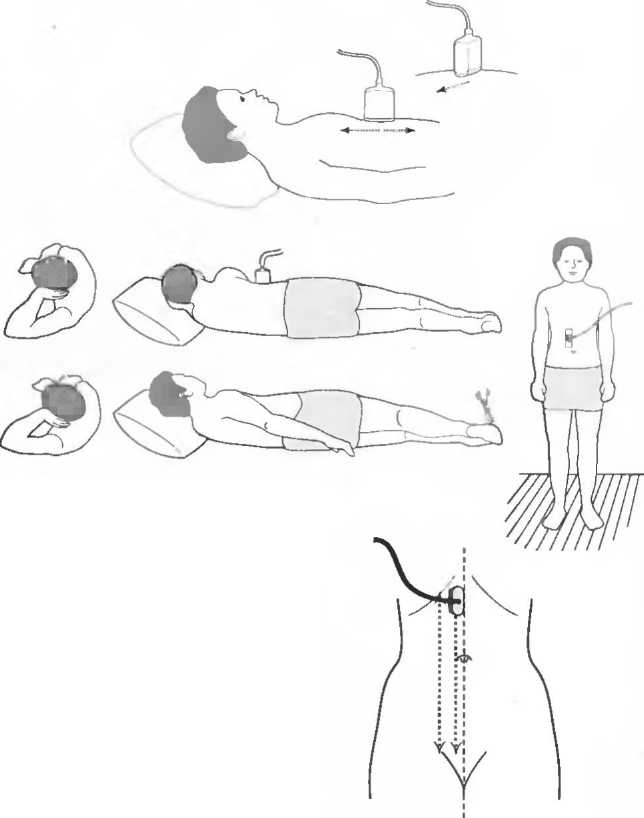

Поперечный срез (аксиальный срез) |

Ультразвуковой срез под прямым углом к длинной оси тела. Термин «аксиальный» обычно используется при обозначении срезов мозга, «поперечный» — при обозначении срезов живота и шеи. Плоскость сканирования может быть перпендикулярной или направленной немного под углом к голове или ногам пациента. Поперечный срез может быть получен в положении пациента на спине, на животе, в положении стоя или на боку. |

Продольный эхографический срез (сагиттальный скан) |

Вертикальный срез по длинной оси тела. Термин «сагиттальный» используется при сканировании в срединной плоскости, особенно при исследовании мозга. Ориентирами, через которые проходит срединная плоскость, являются нос, лобковый симфиз, позвоночник. В случае, если срез не проходит в срединной плоскости, он может называться «парасагиттальным». Термин «продольный» чаще используется при исследовании живота и шеи. Продольный срез также может быть получен в положении пациента на спине, на животе, в вертикальном положении, в положении на боку. |

Срез во фронтальной плоскости |

Плоскость, проходящая через тело по длинной оси (от головы до ног) под прямым углом к срединной плоскости. Чтобы сделать зхографический срез в этой плоскости, необходимо поместить датчик на боковую поверхность тела, направив его к другой боковой поверхности, перемещая его параллельно длинной оси тела. Срез во фронтальной плоскостиможет быть получен в положении пациента на спине, на животе, стоя или лежа на боку. |